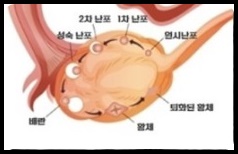

다낭성 난소증후군

난소 내 성장난포가 정상범위보다

많이 존재하는 질환으로

원인은 정확하지 않으나

난소의 호르몬 불균형으로 추정하며

가임기 여성의 발병률이 5~10% 정도로

흔한 질병이며

배란장애나 희발 배란이 있는 여성에게

다낭성 난소의 초음파 소견이나

고안드로겐 혈증이 있는 경우 진단합니다